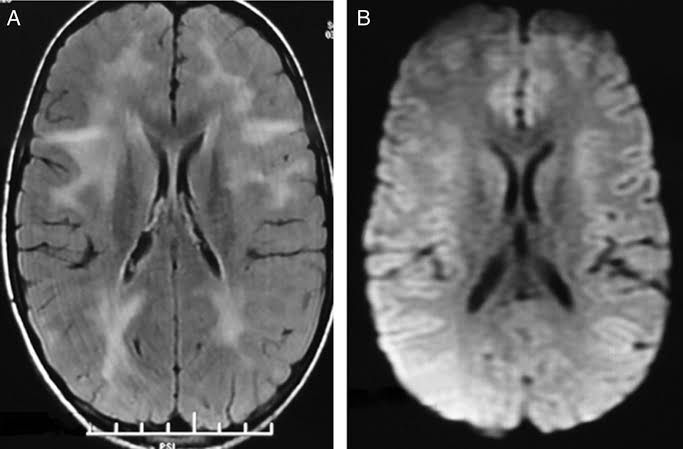

Subacute sclerosing panencephalitis (SSPE) is a progressive neurological disorder of children and young adults that affects the central nervous system (CNS). It is a slow and persistent viral infection related to measles.Most children with SSPE have a history of measles infection at an early age, usually younger than age 2, followed by a latent period of six to eight years before neurological symptoms begin. The initial symptoms of SSPE are subtle and include the following: Mild cognitive decline (such as memory loss) Changes in behavior (such as irritability) Disturbances in motor function, including uncontrollable jerking movements of the head, trunk or limbs called myoclonic jerks Seizures may occur Some people may go blind Good nursing care is the most important aspect of treatment for SSPE, along with anticonvulsant and antispasmodic drugs when needed.